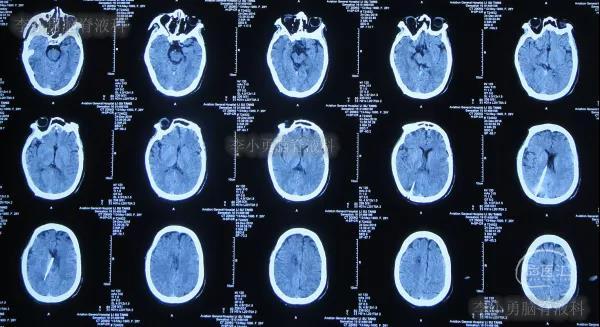

家属为进一步明确病因即2016年4月4日,第2次就诊并住入第二家的上海市静安区的某三甲医院,复查头颅影像后(图-3、图-4),给予按癫痫进行治疗。

图-3:2016年4月4日头颅CT